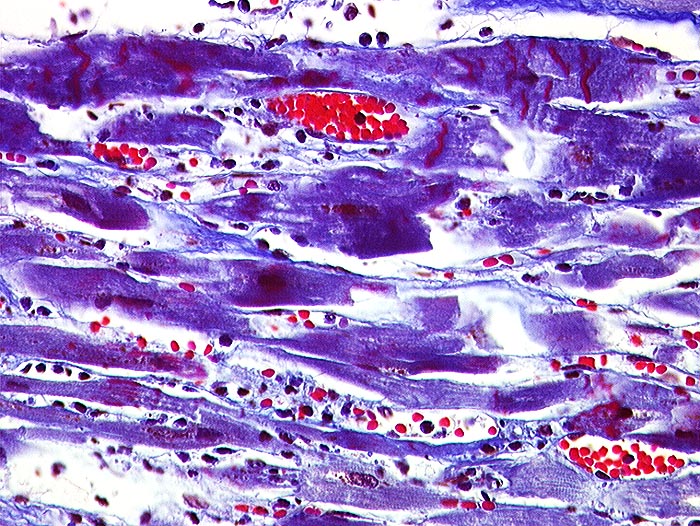

AP/ Akuter Myokardinfarkt

Akuter Myokardinfarkt

vaskulär / Durchblutungsstörung

Kardiovaskuläres System

Herz links

Makroskopie

Pathologischer Befund